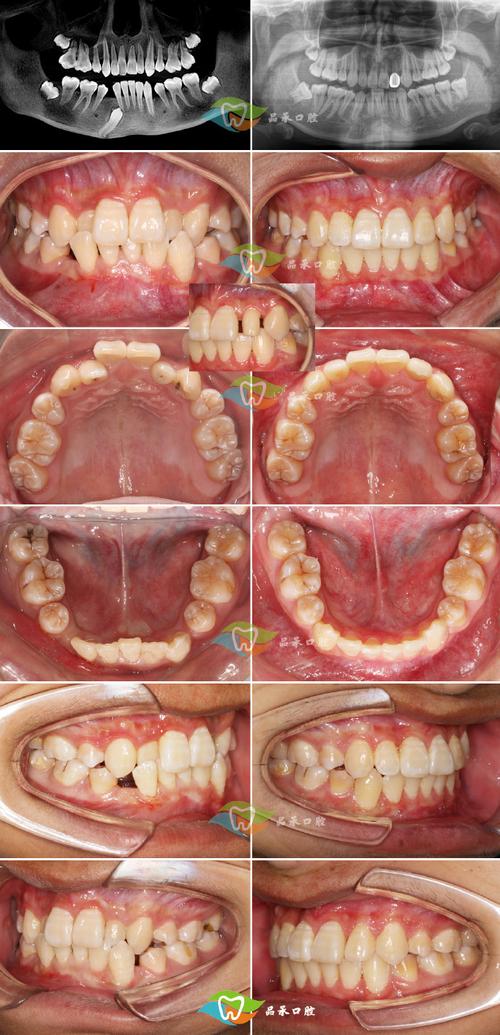

- 口内照片: 牙齿、咬合、面部微笑照等。

- X光片: 根尖片、曲面断层片。

- 头影测量片: 必需!用于分析骨骼、牙齿、软组织的关系,是制定方案的核心依据。

- CBCT: 对于复杂病例(如骨性畸形、埋伏牙、颞下颌关节问题等)通常需要拍摄,提供三维信息。

- 牙模型: 传统取模或口内扫描获取数字模型。